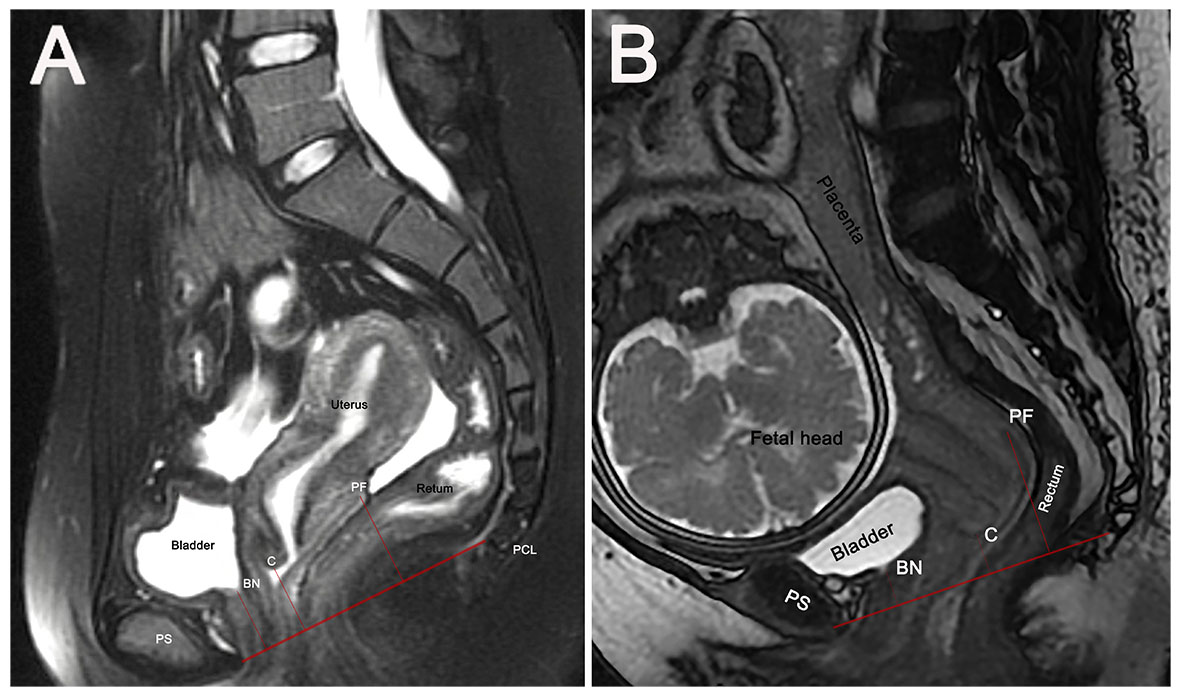

An additional line drawn from the pubic symphysis’ superior margins to the sacral promontory defines the pelvic inlet plane for pregnant women [20]. The depth of the fetus and its appendages in the pelvis was defined as the greatest distance from the pelvic inlet plane to the fetal presentation or the inferior part of the placenta or amniotic sac (Fig. 2). All measurements were performed in millimeters.

Fig. 2. Engagement depth of fetal/placental structures relative to pelvic inlet plane. (A) Cephalic presentation with shallow engagement (Depth = 22 mm). (B) Cephalic presentation with deep engagement (Depth = 65 mm; amniotic sac as the most inferior part entering the pelvis). (C) Placenta previa (Depth = 40 mm; placenta as the most inferior part entering the pelvis). (D) Breech presentation (Depth = 60 mm; amniotic sac as the most inferior part entering the pelvis). Blue solid line: Pelvic inlet plane, drawn from the superior margin of the pubic symphysis to the sacral promontory. Blue dashed line: Parallel to the pelvic inlet plane, passing through the lowest point of the fetus or its associated structures. Depth: Perpendicular distance between the two parallel lines, quantifying the extent of fetal/placental descent into the pelvis. Red solid line: Pubococcygeal line (PCL).